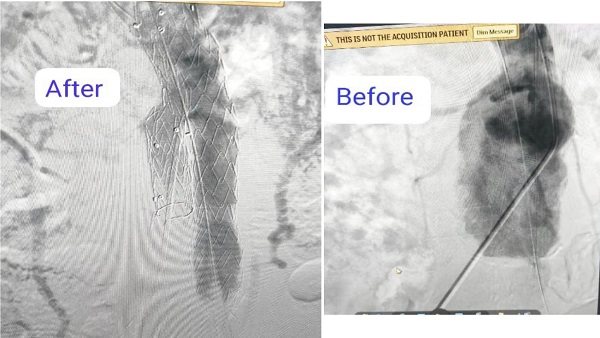

نجح فريق بقسم جراحة الأوعية الدموية بمستشفى بدر التابعة لكلية الطب بجامعة حلوان في إجراء تركيب قسطرة دقيقة جدًا لمريض يعاني من تمدد كبير في الشريان الأورطي والشريان الحرقفي الايمن، حيث تم تثبيت دعامات مغطاة على هذين الشريانين لمنع انفجارهما، مما ساهم في إنقاذ حياته.